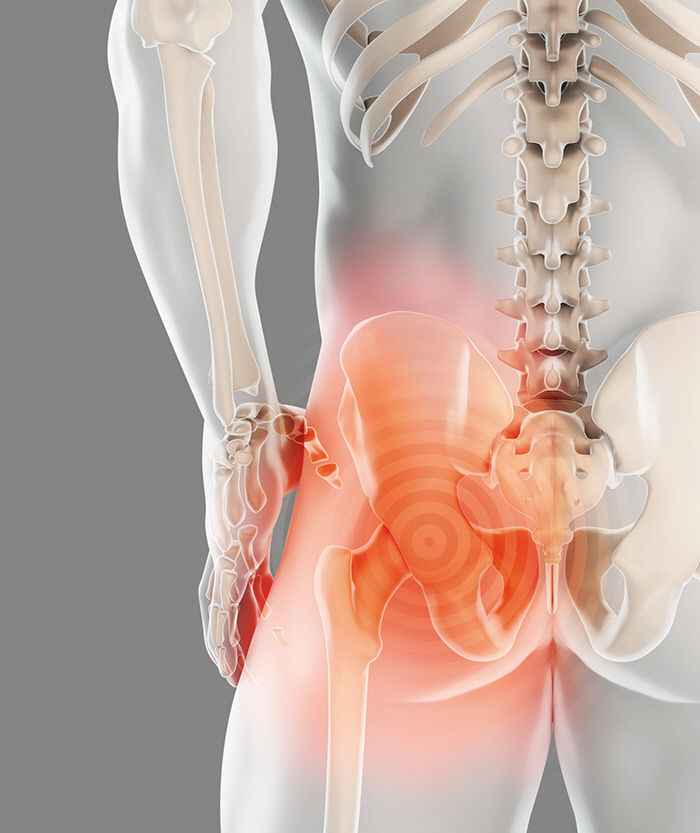

골반통증, 방치하면 큰 병 된다? 최근 들어 허리와 엉덩이 부위에서 느껴지는 ‘골반통증’ 때문에 고생하는 사람들이 늘고 있습니다. 특히 출산 후 여성이나 40대 이후 중년 여성에게 자주 나타나는 현상입니다.

이는 잘못된 자세로 장시간 앉아 있는 경우 근육 및 인대가 늘어나거나 손상돼 생길 수 있으면, 또한 평소 다리를 꼬고 앉거나 양반다리를 하고 앉는 습관도 골반통증의 원인이 될 수 있습니다.

하지만 대부분의 사람들은 이를 일시적인 근육통 정도로 생각하고 대수롭지 않게 여기곤 합니다. 그러나 문제는 골반통증을 그대로 방치할 경우 척추질환으로까지 이어질 수 있다는 점입니다.

4. 근골격계 원인

골반저 기능 장애 및 근육 긴장과 같은 골반 부위와 관련된 근골격계 문제는 골반 통증을 유발할 수 있습니다. 골반저 기능 장애는 골반 장기를 지지하는 근육, 인대 및 결합 조직에 문제가 생기는 것을 말합니다.

이러한 근육이 긴장하거나 해당 부위에 부상을 입으면 골반 쪽에 지속적인 통증이 발생할 수 있습니다.